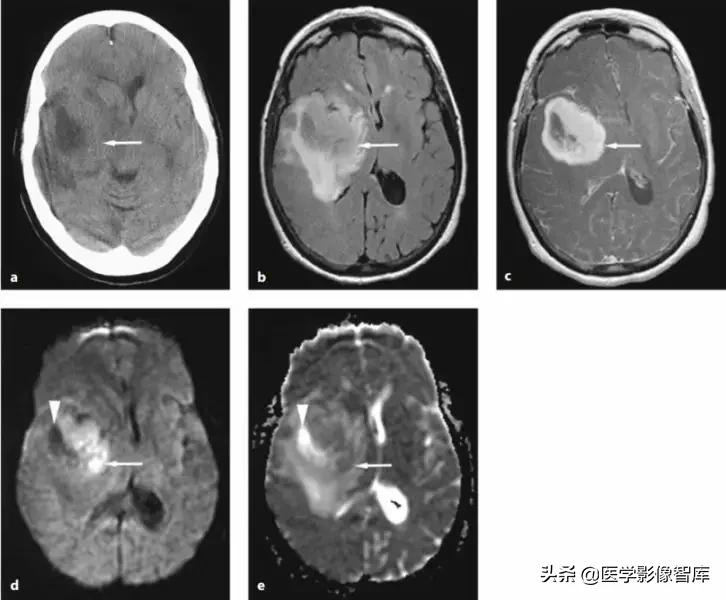

图4 环形强化病灶对比

DWI是鉴别脑脓肿与高级别胶质瘤、转移瘤等良好手段。对于上图两个病例,其实加做一个DWI序列的话,就很好区分。左图患者DWI明显高信号,ADC图低信号,是脑脓肿;右图患者DWI低信号,ADC图高信号,是脑肿瘤。

图5 环形强化对比(脑脓肿 vs 胶质母细胞瘤)